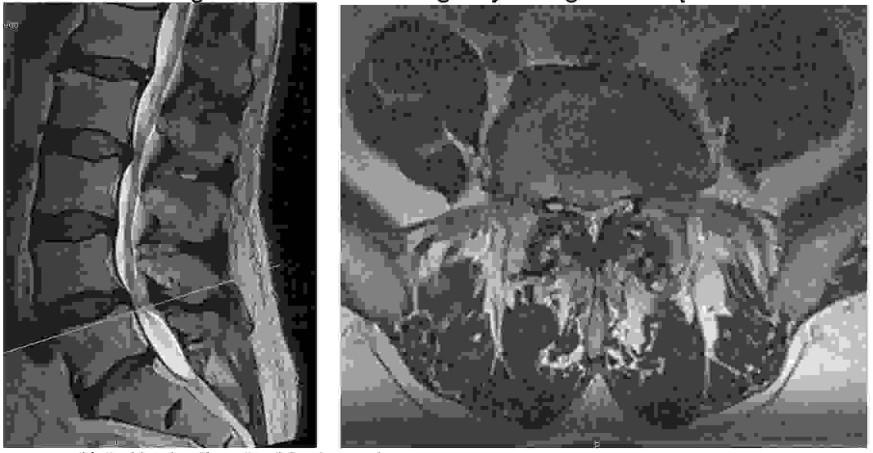

Do charakterystycznych objawów patologii widocznej na poniższych obrazach tomografii rezonansu magnetycznego należą: 1) ból okolicy lędźwiowej, 2) parestezje, ból promieniujący do kończyn dolnych w pozycji stojącej podczas chodzenia, 3) osłabienie siły zgięcia stawu biodrowego, 4) osłabienie odruchu kolanowego, 5) zmniejszenie dolegliwości bólowych promieniujących do kończyn dolnych po przyjęciu pozycji siedzącej.